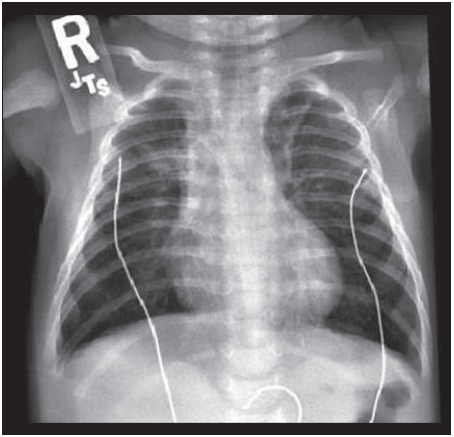

On the third day of hospitalization for lethargy and respiratory distress after smoke inhalation during a house fire, a 2-month-old girl became febrile, with a temperature of 38.5ºC (101.3ºF).